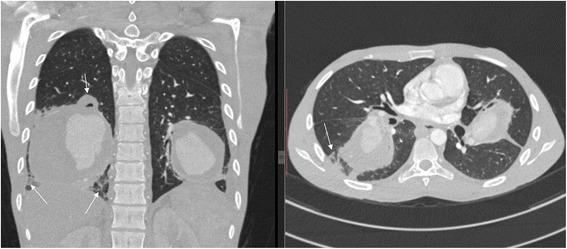

A 24-year-old man, a nursing student of African descent, was referred to us from an up-country regional hospital with a 4-week history of recurrent episodes of breathlessness, awareness of heartbeats and coughing blood 3 weeks after completing a 6-month course of anti-tuberculosis drugs. A physical examination revealed conjuctival and palmar pallor but there were no stigmata of connective tissue disorders, systemic vasculitides or congenital heart disease. An examination of the cardiovascular system revealed accentuated second heart sound (S) with early diastolic (grade 1/6) and holosystolic (grade 2/6) murmurs at the pulmonic and tricuspid areas respectively. Blood tests showed iron deficiency anemia, prolonged bleeding time, and mild hyponatremia. A chest radiograph revealed bilateral ovoid-shaped perihilar opacities while a computed tomography scan showed bilateral multiple pulmonary artery pseudoaneurysms with surrounding hematoma together with adjacent cystic changes, consolidations, and tree-in-bud appearance. Our patient refused to undergo surgery and died of aneurismal rupture after 9 days of hospitalization.

一名24岁的男性,是一名非洲裔护理专业学生,在完成6个月抗结核药物疗程3周后,因反复出现气短、心悸和咯血4周,被一家偏远地区医院转诊至我院。体格检查发现结膜和手掌苍白,但无结缔组织病、系统性血管炎或先天性心脏病的体征。心血管系统检查发现第二心音亢进(S),分别在肺动脉和三尖瓣区有舒张早期(1/6级)和全收缩期(2/6级)杂音。血液检查显示缺铁性贫血、出血时间延长和轻度低钠血症。胸部X线片显示双侧肺门周围椭圆形阴影,而计算机断层扫描显示双侧多发肺动脉假性动脉瘤伴周围血肿,以及相邻的囊性改变、实变和树芽征。我们的患者拒绝接受手术,住院9天后死于动脉瘤破裂。